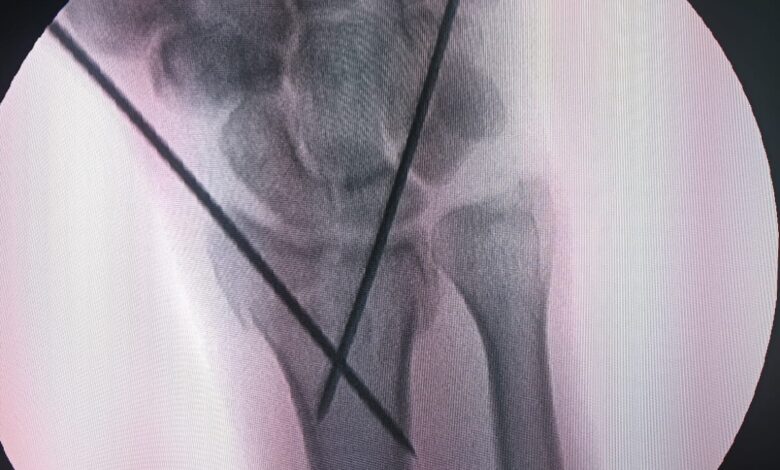

सिविल सर्जन सह मुख्य अस्पताल अधीक्षक राजगढ़ डॉ. राजनीश शर्मा द्वारा बताया गया कि जिला चिकित्सालय राजगढ़ में आधुनिक चिकित्सा सुविधाओं की दिशा में एक महत्वपूर्ण कदत उठाते हुए सी-आर्म मशीन की मदद से सफल सर्जरी की गई। यह सर्जरी नरसिंहगढ़ तहसील निवासी श्री रामबाबू उम्र 65 वर्ष पर की गई। जिसकी हाथ की कलाई में फैक्चर था। जानकारी के अनुसार श्री रामबाबू को बुधवार को जिला चिकित्सालय में भर्ती कराया गया था। जहां जांच के बाद डॉक्टरों ने उनकी कलाई की हडडी में फेक्चर पाया और सर्जरी का निर्णय लिया। जिसके बाद शुक्रवार को ऑर्थोपेडिक सर्जन डॉ. अदित अग्रवाल ने सी-आर्म मशीन की सहायता से सफल ऑपरेशन किया।

क्या है सी-आर्म मशीन :- सी-आर्म मशीन एक अधुनिक एक्सरे इमेजिंग तकनीक है। जिससे ऑपरेशन के बीच में हडडियों की स्थिति को लाइव देखा जा सकता है। इससे सर्जरी अधिक सटीक और सुरक्षित हो जाती है। इस तकनीक के उपयोग से डॉक्टरों को ऑपरेशन के दौरान बार-बार एक्सरे लेने की जरूरत नहीं पड़ती और मरीज को भी कम जोखित रहता है। ऑर्थोपेडिक सर्जन डॉ. अग्रवाल ने बताया कि इस मशीन की मदद से ऑपरेशन के दौरान हड्डी की सही स्थिति का तुरंत पता चल जाता है। जिससे बेहतर परिणाम मिलते है। उन्होंने कहा कि जिला चिकित्सालय में इस तरह की सुविधा उपलब्ध होने से क्षेत्र के मरीजों के लिए बड़ी राहत की बात है। आगामी समय में और भी जटिल ऑपरेशन आसानी से किये जा सकेंगे। जिला चिकित्सालय में बड़ी संख्या में फैक्चर के मरीज इलाज कराने पहुंचते है। जिसमें से अधिकांश मरीजों को रेफर करना पड़ता है। लेकिन अब सी-आर्म मशीन की सहायता से जटिल ऑपरेशन भी जिला अस्पताल में किये जा सकेंगे